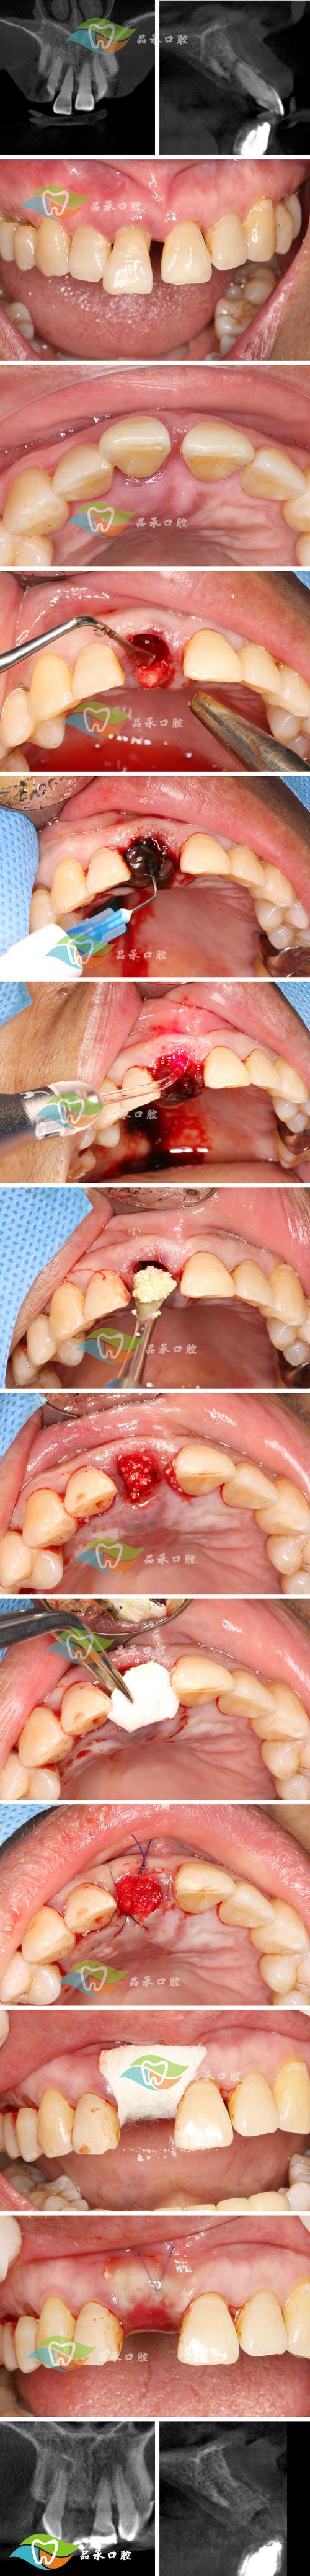

牙槽骨植骨粉手术的步骤

手术需在严格无菌条件下进行,通常由口腔外科或种植专科医生操作,具体流程包括:

麻醉与切口

- 局部浸润麻醉或神经阻滞麻醉,确保手术区域无痛。

- 在缺牙区牙槽嵴顶做“梯形”或“弧形”切口,切开黏骨膜,翻瓣暴露骨缺损区域,彻底清除肉芽组织或炎性组织。

骨缺损处理与植骨

- 用球钻或超声骨刀修整骨缺损边缘,形成新鲜创面,促进骨细胞附着。

- 根据缺损大小选择合适植骨材料:若为颗粒状骨粉,可直接填入缺损区;若需支撑形态(如上颌窦提升),可配合使用骨胶原膜或钛网塑形。

- 植骨时需过度补偿(约10%-15%),因材料后续会有一定吸收,确保最终骨量满足种植需求。

屏障膜覆盖与缝合

- 在植骨材料表面覆盖可吸收胶原膜(如Bio-Gide)或不可吸收膜(如钛膜),防止软组织长入骨缺损区,为骨再生提供空间。

- 将黏骨膜瓣复位,用可吸收缝线(如 Vicryl)严密缝合,关闭创口,避免植骨材料暴露。